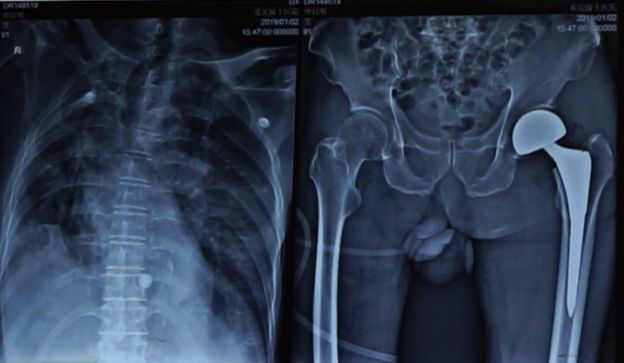

人民日报市场报《时事经济观察》2月20日综合讯 91岁的钟爷爷行走时不小心摔倒,导致左侧股骨颈骨折。这种骨折被称为,老人的“最后一次骨折”。 治好了,便能行走如初,治不好,可能出现股骨头缺血坏死,而终身不能行走。 近日,重庆骑士医院骨科专家们采用前沿微创术式——直接前方入路,仅用30分钟时间,便为高龄老人精准完成了左髋关节置换手术,让老人走了起来。 医者仁心 为患者挑战高风险手术 原兰州军区陆军第25医院骨科主任,现任重庆骑士医院骨科学科带头人——严兵主任介绍到,目前治疗股骨颈骨折常选的方法是人工髋关节置换,而钟爷爷患有严重骨质疏松,脆弱的骨骼如同“豆腐渣”,要为他进行关节置换和内固定,无疑对麻醉和手术需提出更高的要求。 而让手术难度加大的又何止这些,老人患有多种基础疾病:慢阻肺、肺气肿、肺部感染、心律失常以及脑梗塞。 随便一个疾病,都可能带来严重的后果。 严主任介绍:“为了缩短康复时间,我们采用的微创新术式,显著降低了传统后路手术的创伤和并发症。” 日前,钟爷爷已经在医护人员的建议下开始下床行走,接受康复训练。